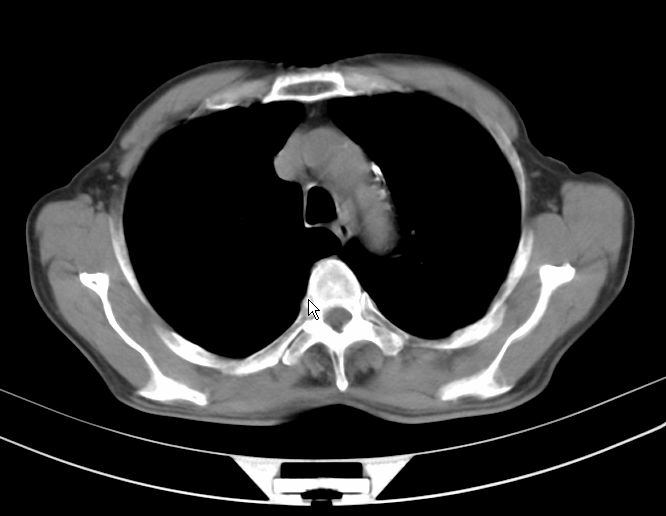

请大家看看是什么性质的。炎性病变首先考虑哪一种炎症。

支持右肺上叶前段\\下叶内基底段感染,建议抗炎治疗后复查,除外结核.

支持右肺上叶前段\\下叶上段感染,建议抗炎治疗后复查,除外结核.

支持右肺上叶前段、下叶内基底段感染,建议抗炎治疗后复查,除外结核.

右肺上叶前段及下叶内基底段感染性病变;建议抗炎治疗后复查。

楼主说是炎症,凭啥?典型的周围型肺癌(腺癌可能性大),肝内可能已有转移,强化看看吧。